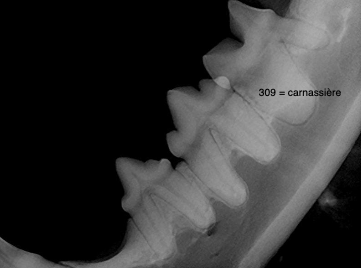

Quel est l’index parodontal de la dent 309 avec gencive un peu inflammée?

A

PD1

Théorie :

- PD0 = parodonte sain, pas de perte osseuse

- PD1 = gingivite, pas de perte osseuse

- PD2 = parodontite < 25% perte osseuse

- PD3 = parodontite 25-50% ou furcation 2

- PD4 = parodontite > 50% ou furcation 3